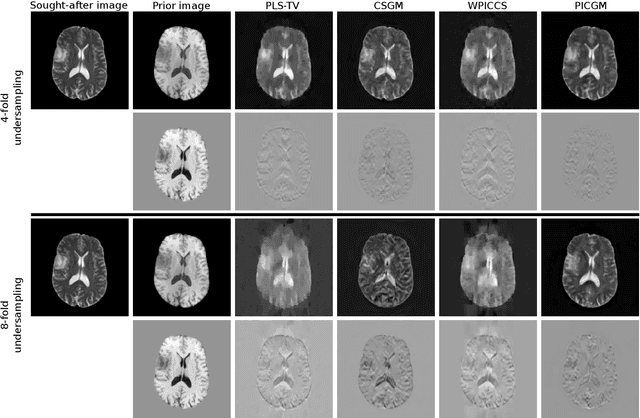

Abstract:Computed medical imaging systems require a computational reconstruction procedure for image formation. In order to recover a useful estimate of the object to-be-imaged when the recorded measurements are incomplete, prior knowledge about the nature of object must be utilized. In order to improve the conditioning of an ill-posed imaging inverse problem, deep learning approaches are being actively investigated for better representing object priors and constraints. This work proposes to use a style-based generative adversarial network (StyleGAN) to constrain an image reconstruction problem in the case where additional information in the form of a prior image of the sought-after object is available. An optimization problem is formulated in the intermediate latent-space of a StyleGAN, that is disentangled with respect to meaningful image attributes or "styles", such as the contrast used in magnetic resonance imaging (MRI). Discrepancy between the sought-after and prior images is measured in the disentangled latent-space, and is used to regularize the inverse problem in the form of constraints on specific styles of the disentangled latent-space. A stylized numerical study inspired by MR imaging is designed, where the sought-after and the prior image are structurally similar, but belong to different contrast mechanisms. The presented numerical studies demonstrate the superiority of the proposed approach as compared to classical approaches in the form of traditional metrics.

Abstract:Obtaining an accurate and reliable estimate of an object from highly incomplete imaging measurements remains a holy grail of imaging science. Deep learning methods have shown promise in learning object priors or constraints to improve the conditioning of an ill-posed imaging inverse problem. In this study, a framework for estimating an object of interest that is semantically related to a known prior image, is proposed. An optimization problem is formulated in the disentangled latent space of a style-based generative model, and semantically meaningful constraints are imposed using the disentangled latent representation of the prior image. Stable recovery from incomplete measurements with the help of a prior image is theoretically analyzed. Numerical experiments demonstrating the superior performance of our approach as compared to related methods are presented.